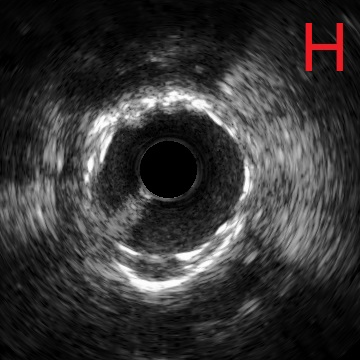

对冠状动脉造影及IVUS图像进行综合判断,已经具备安全进行冠状动脉支架治疗的条件,于是在病变处植入支架治疗,随后在IVUS指导下采用后扩球囊改善贴壁情况,最终支架膨胀理想,顺利完成手术(图G、H)。